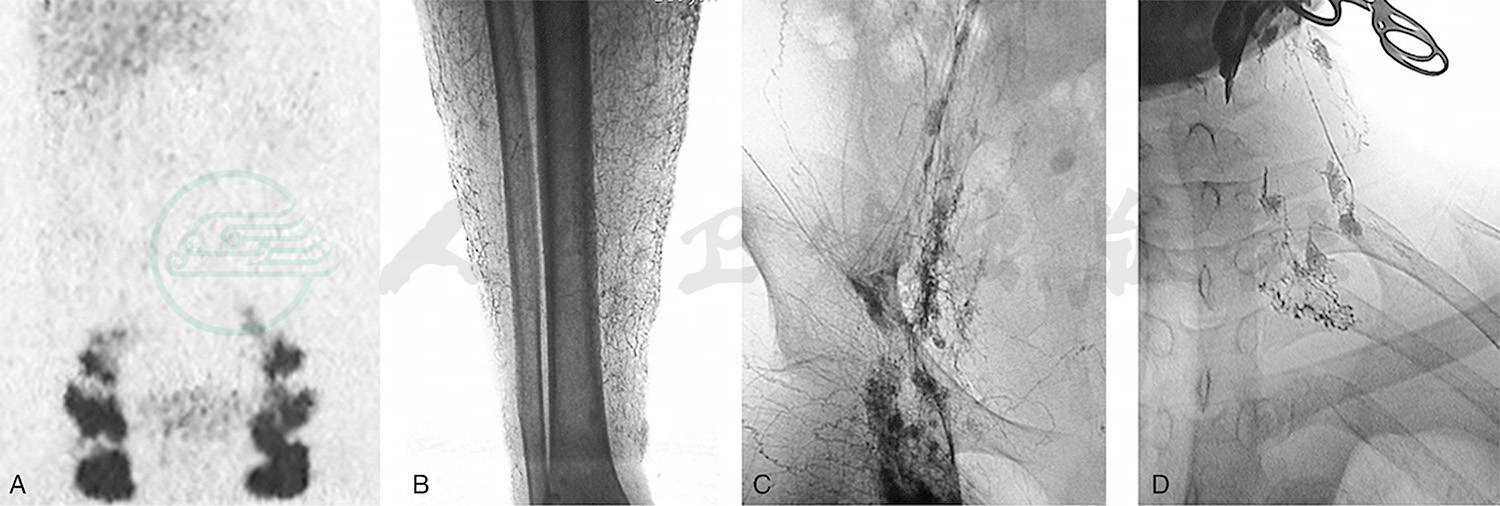

我组乳糜性腹水病例中,有一对来自吉林的母子同患乳糜性腹水,影像学均表现为原发性腹膜后淋巴管发育不全。儿子同时有乳糜性胸水和下肢淋巴水肿(图1)。

图1母子同患乳糜胸腹水

母亲45岁,A.核素淋巴显像:腹股沟淋巴结核素浓聚,腰淋巴干未显影。儿子18岁,伴有右下肢淋巴水肿,经右足背直接淋巴管造影显示:B.右下肢淋巴水肿,小腿淋巴管网状扩张;C.腹膜后淋巴管发育不全,右腹股沟有淋巴管侧支代偿形成;D.经右耳后淋巴管直接淋巴管造影显示:颈干形成不全,未汇入颈静脉角区域,并向颈前反流。母亲保守治疗腹水消失,儿子行腹腔静脉转流术良好控制